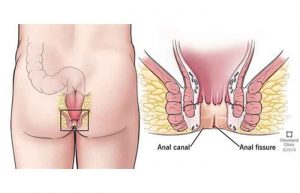

عمل لیزر فیشر یا شقاق چگونه انجام میشود؟

راه های درمان شقاق مقعدی